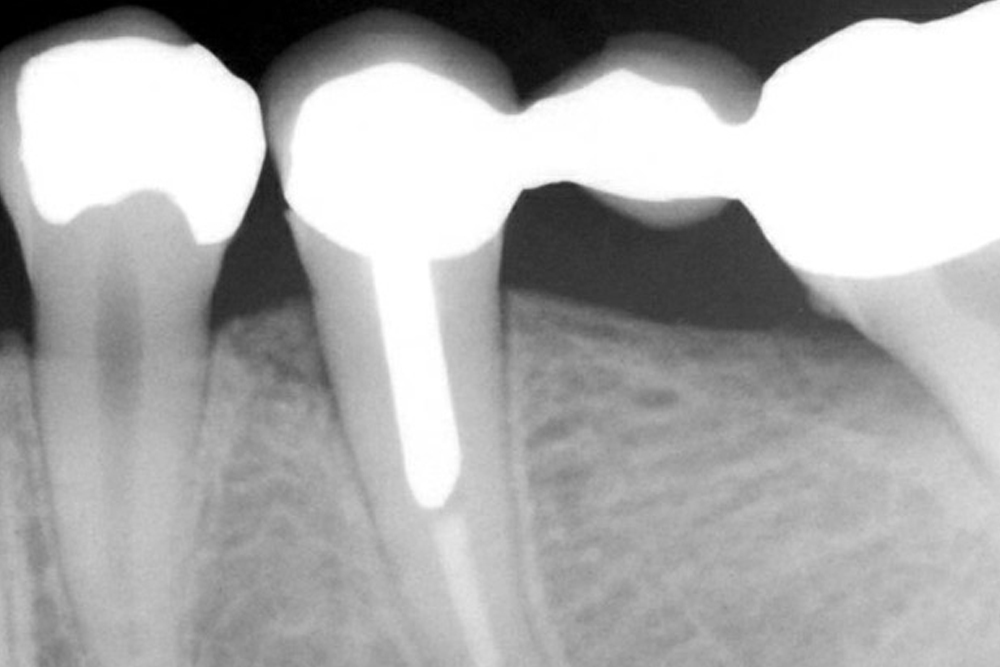

Le nostre apparecchiature diagnostiche sono minimamente invasive. Per le videoradiografie usiamo sensori di ultima generazione che evitano lo sviluppo di lastre fotografiche riducendo del 90% l’emissione di raggi X necessari per l’esame.

L’ortopantomografo digitale presente nel nostro studio consente di ottenere, nel giro di pochi secondi, la radiografia panoramica computerizzata del paziente, con bassissime dosi di radiazioni.